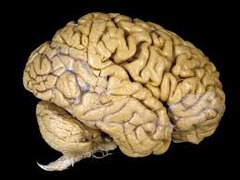

Necrotic Lesion